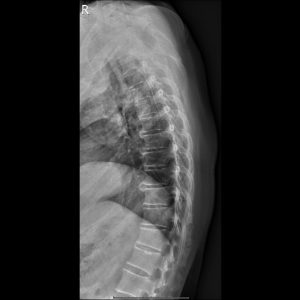

L-spine AP view

L LAT.Seq2.Ser1.Img1

L-spine Lateral view

L-spine Oblique view(RPO)

L-spine Oblique view(LPO)​

L-spine Lat Ext.

L-spine Lat. Flex.